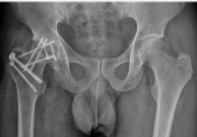

This case report follows a 13-year-old girl who present with pain in the left hip region for 2 months along with difficulty in walking. No associate significant contributory history. Radiograph was s/o a solid cystic lesion on the proximal femur. Magnetic resonance imaging (MRI) contrast scan of left thigh with femur done s/o well marginated expansile altered signal intensity lesion in proximal diaphysis of left femur with few cystic changes within with break and thinning of cortex at places with periosteal reaction around the lesion. Core biopsy was done s/o Aneurysmal Bone Cyst for which she undergone curettage of bony cyst with bone grafting (fibula) with Intra-Medullary nailing as shown in Fig. 1. Post-operatively she developed fever with wound gets infected with some discharge. Treated with higher antibiotics and daily cleaning and dressing. Fever subsided but continuous discharge from wound present.

Figure 1: Pre-operative Radiograph showing a multicasting lesion in the left proximal femur, Radiograph of post-curettage with fibula grafting with nailing.

Post-operative course was uneventful with drain removed on post-operative day 3 and PT discharged on post-operative day 5. Abductor muscle strengthening exercises started on bed on post-operative day 2 without weight bearing. Post-operative X-ray showing well fitted prosthesis as shown in Fig. 5. Four weeks bed rest given for healing of mesh then started full-weight-bearing mobilization with walker f/b stick support and then without support. Strengthening and range of motion exercise titrated for individual need. Past follow-up was in June 2025. As patient attained menarche there will be low chance of limb length discrepancy, but even if occurred can be managed conservatively by shoe lift. Follow-up will be 6 monthly with radiograph of local site for recurrence with contrast-enhanced computed tomography (CT) thorax for metastasis.